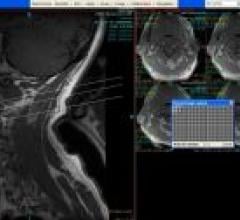

Despite decades of progress in breast imaging, one challenge continues to test even the most skilled radiologists ...